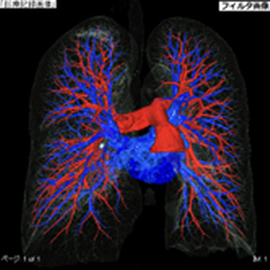

CTの検査画像例

CT装置を大幅にグレードアップ

当施設では地域医療の充実を図るため、令和4年9月に県内初となるCanon社製「Aquilion ONE nature edition(320列マルチスライスCT)」を導入しました。320列の検出器を備え、従来の64列CTに比べ大幅に性能が向上。被ばくを抑えながら短時間で高精細な撮影が可能となり、検査精度が向上するとともに、患者さんの負担も軽減されています。

AI技術のアプローチの1つである、Deep Learningを用いて設計した画像再構成技術で、分解能を維持したままノイズを選択的に除去することができます。本技術により、高品質な画像を低線量かつ短時間で提供することが可能となりました。

胸部~骨盤までの撮影を2秒で終えることができる高速撮影モードが選択できます。息止め不能な方や体動のある患者さんに有用です。 また、wide volume撮影を用いることで心臓の検査ではブレの少ない高画質な画像の提供、四肢関節ではアーチファクトの少ない高分解能な画像を短時間で得られるようになりました。